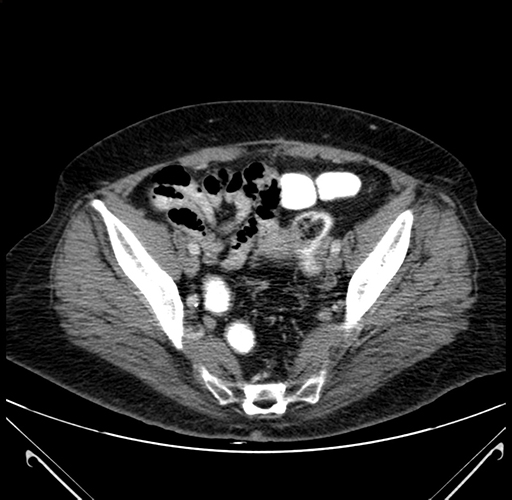

Pre-Chemo: Axial Venous

Axial Venous